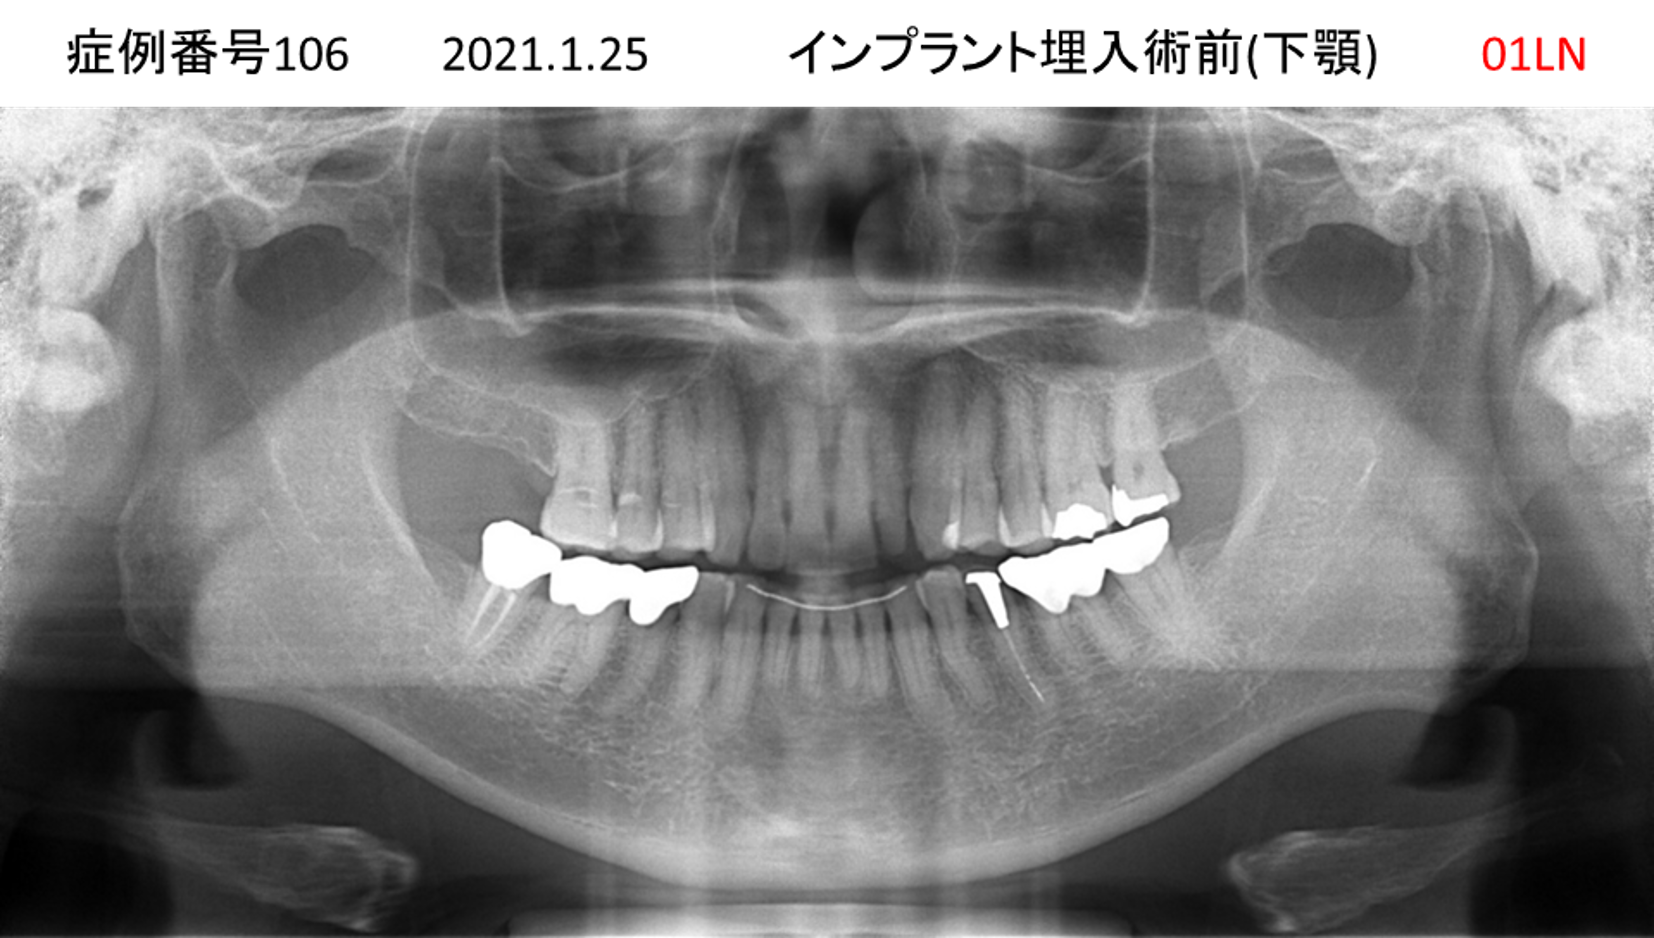

上の前歯が揺れていて痛い患者様のインプラント症例

| 治療名称 |

インプラント |

| 治療費用 |

295万円+税 |

| 治療期間 |

6か月 |

| 患者さんの症状(主訴) |

上の前歯が揺れていて痛い |

| 治療内容 |

抜歯即時インプラント |

| 治療結果 |

痛みがなく、しっかり噛める。 見栄えがとても良い |

| 治療の注意点(リスク/副作用) |

インプラントが壊れたら再治療が必要 |